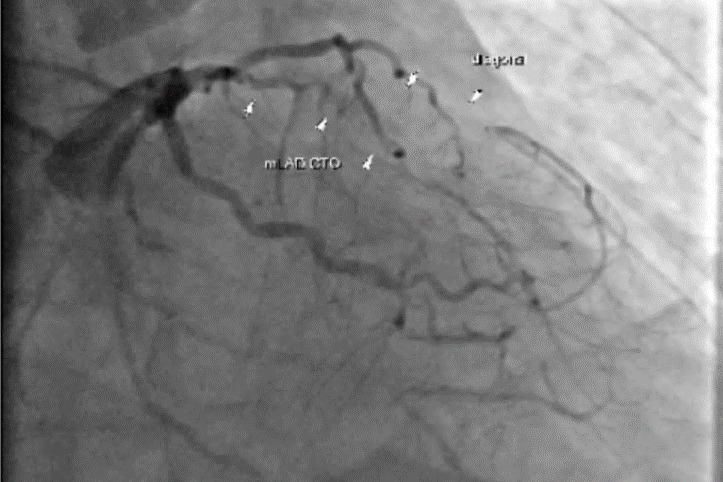

心導管所見,三條冠狀動脈全數堵塞。